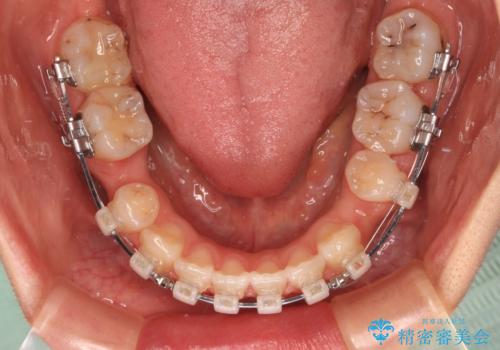

- 矯正装置

- クリアブラケット

- 治療期間

- 2年4ヶ月

口元の突出感が認められ、更には左右で異なる咬合状態であったため、下顎右側は第二小臼歯を、左側は第一小臼歯を抜去することでバランスを取るような治療計画としました。

下顎の抜歯位置を左右で変えることで、最終的に上下正中をほぼ一致させることができました。